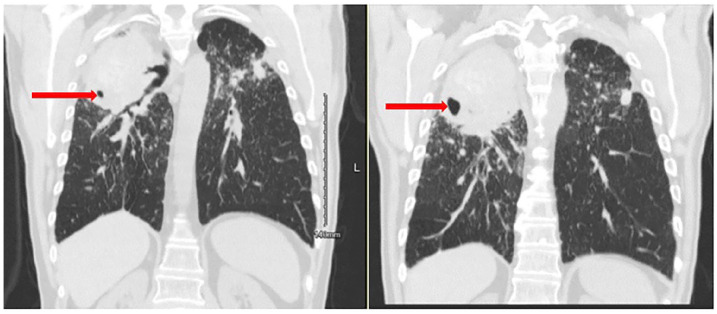

Mycobacterium kansasii is a slow-growing mycobacterium commonly affecting the lungs, usually in a structurally deformed lung. We discuss a case of 67-year-old male with a medical history of complicated coal workers pneumoconiosis or coal mine dust lung disease presented to the pulmonary clinic with worsening dyspnea and hemoptysis with imaging findings revealing cavitary lung lesions in the right upper lobe and progressive massive fibrosis (PMF) bilaterally. Patient sputum gram stain showed acid-fast bacilli, and the cultures grew M. kansasii. He was started on rifampin, ethambutol, and azithromycin. This case highlights the importance of thorough workup of cavitary lung lesion, reinforcing the association of mycobacterium species in a patient with PMF and associated cavities.